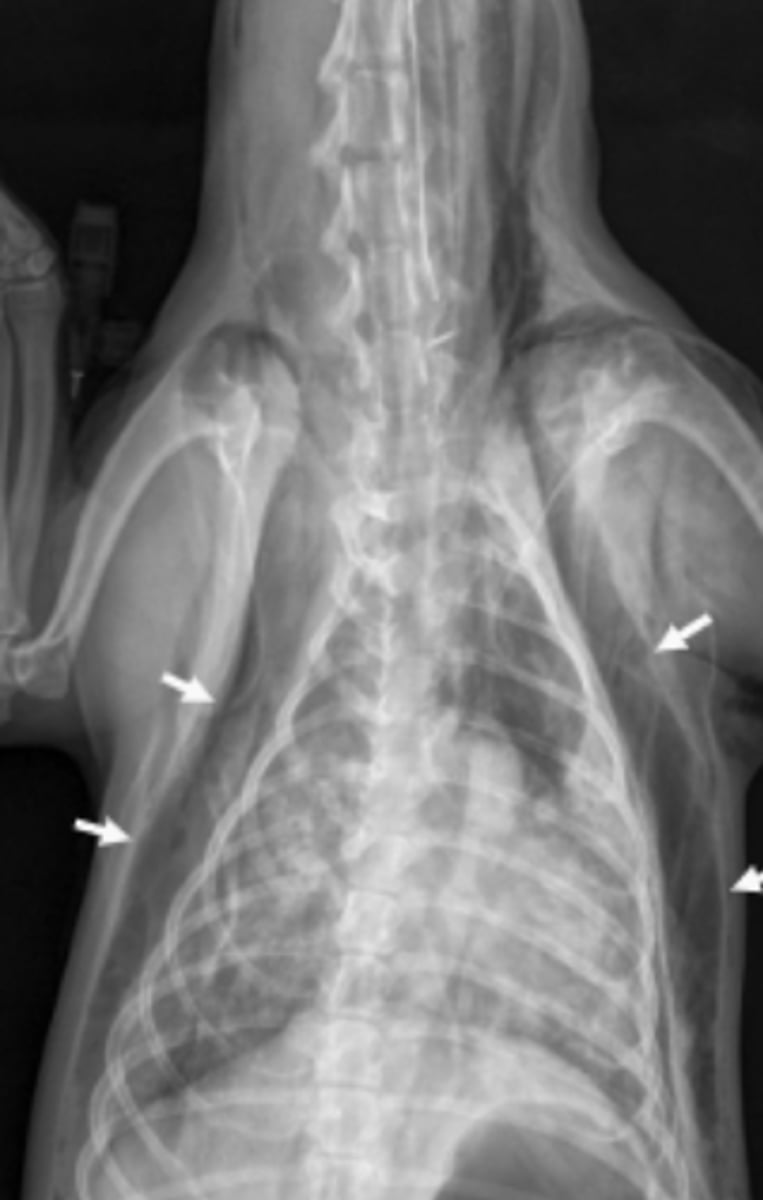

megaesófago

patología:

megaesófago, por cuerpo extraño

neumonía por aspiración por

la parenquíma pulmonar, por riesgo de neumonía por aspiración

si vemos megaesófago en una radiografía, es importante evaluar: